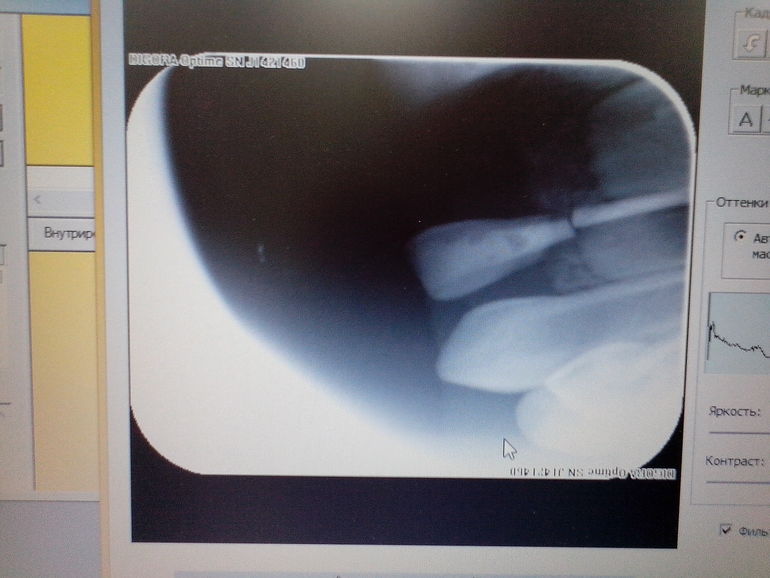

В 2,4 года обратили внимание, что одна лопатка ниже другой и шатается, сделали снимок- двойной перелом корня, плюс на снимке увидели совершенно случайно, что боковой резец рядом с другой лопаткой тоже сломан. Переломы все внутри костницы. Зубы удалили под Севораном. Сейчас ребенку 2г.10мес. Снимки сделаны неделю назад.